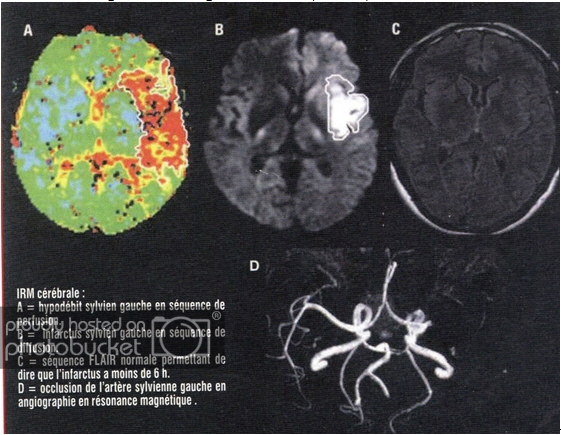

Default ĐỘT QUỴ (STROKE)

ĐỘT QUỴ (STROKE)

BS NGUYỄN VĂN THỊNH